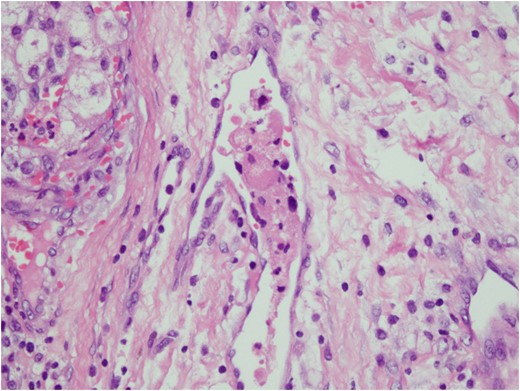

Histologic sections of the mass show distinct variably sized and shaped collections of uniform polygonal tumor cells, separated by fibrovascular septa and delicate capillary-sized vascular channels lined by flattened endothelium at low magnification (Fig. 5). Within the tumor nests, there is loss of cellular cohesion and necrosis of the centrally located cells in the nests results in the pseudo-alveolar pattern (Fig. 6). Vascular invasion is also present (Fig. 7). The individual tumor cells have distinct cell borders and abundant eosinophilic to clear, somewhat granular cytoplasm surrounding a central nucleus with variably sized nucleolus. Nuclear atypia is rarely seen. Mitotic figures are uncommon. The cells contain rhomboid or rod-shaped crystalline inclusions that are faintly apparent on routine histology and are better demonstrated with periodic acid-Schiff stain after diastase digestion (Fig. 8).

Tumor cells are arranged in organoid or nesting pattern. The nests are vary in size and shape and are separated by delicate thin fibrous septa containing vascular channels.

Loss of cellular cohesion and necrosis of the centrally located cells in the nests.